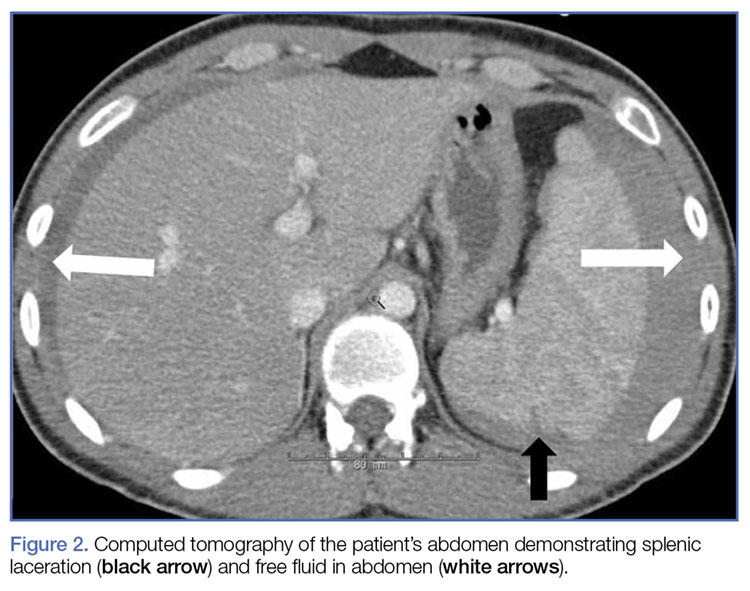

A: Traumatic splenic laceration is diagnosed through physical examination, imaging tests, and blood tests to check for signs of internal bleeding.